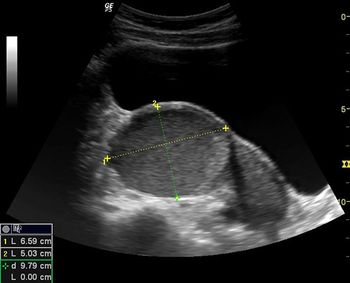

This second-trimester fetus has a renal abnormality. Can you identify it?